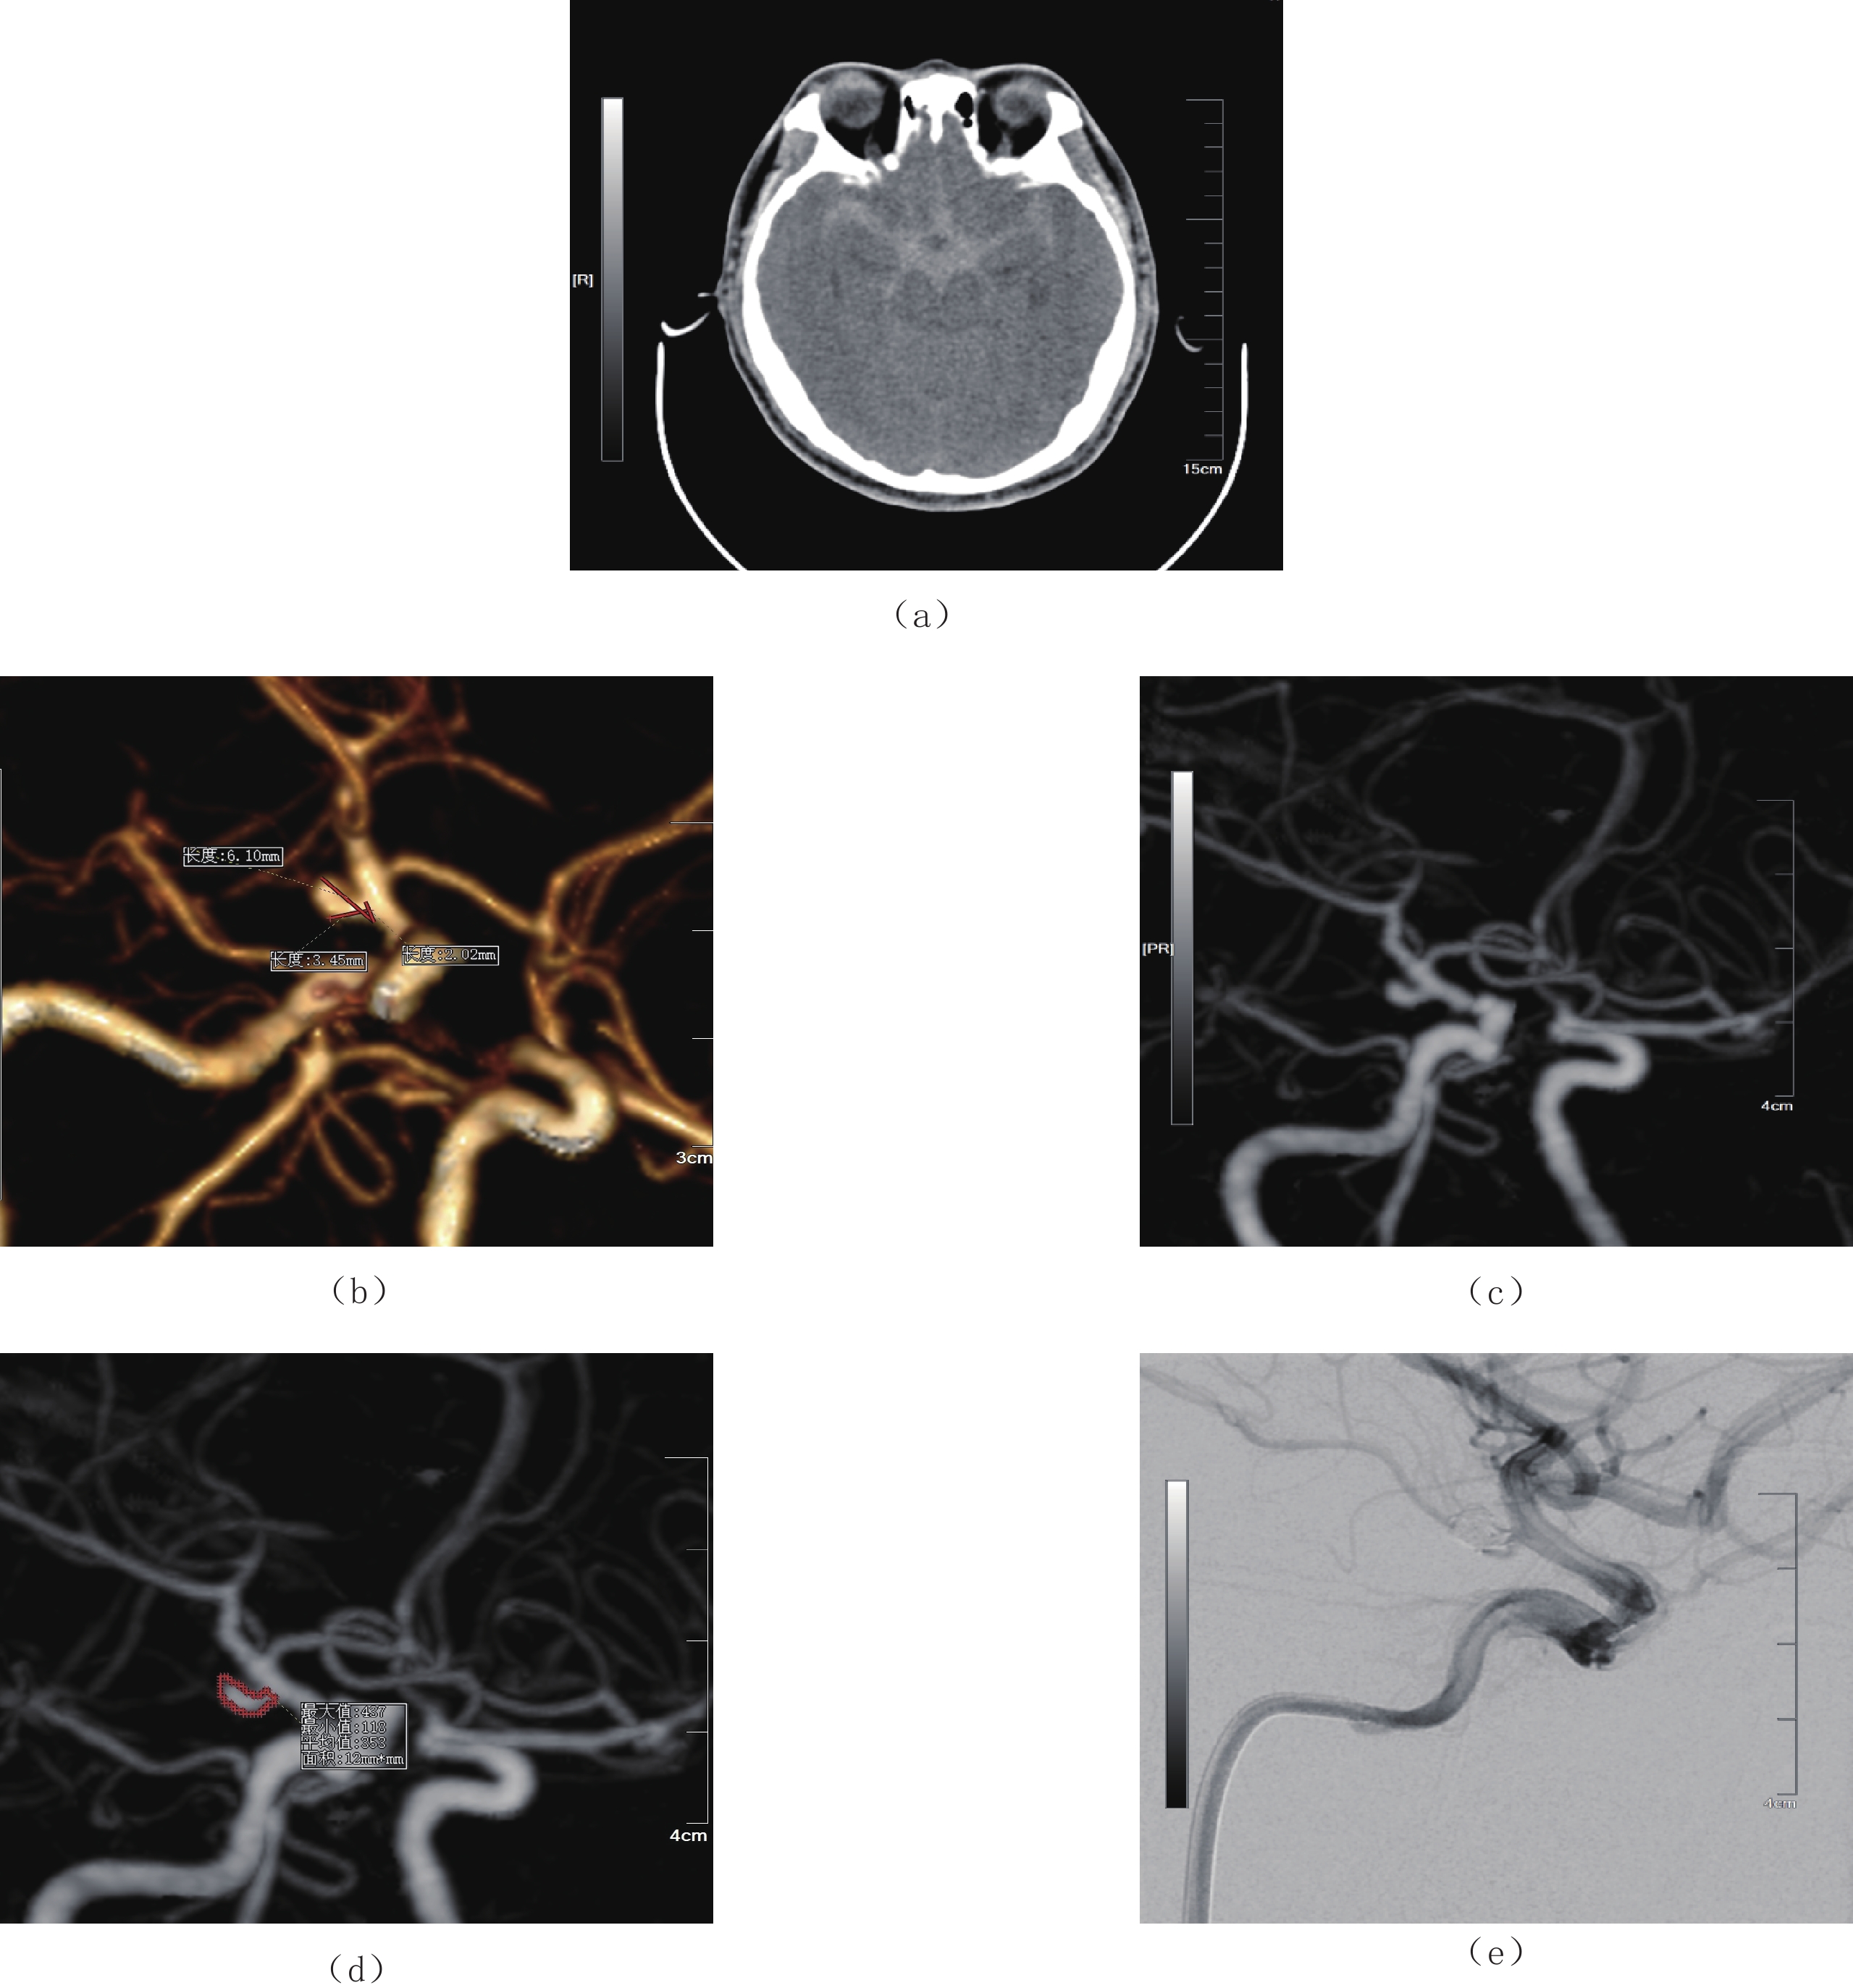

目的:探讨CT血管造影(CTA)在颅内动脉瘤破裂风险评估中的应用价值及形态学特征。方法:选取2018年10月至2021年10月蚌埠医学院第三附属医院颅内动脉瘤患者82例,所有研究对象均通过西门子64排128层螺旋CT及西门子数字减影血管造影(DSA)机实施CTA检查及DSA检查。统计分析本组患者瘤体破裂情况、不同瘤体破裂情况者形态学特征,并分析颅内动脉瘤瘤体破裂影响因素。结果:本组82例颈动脉患者瘤体破裂率为74.39%(61/82)、瘤体未破裂率为25.61%(21/82);瘤体破裂者子囊数目(60.66%)、面积比、SR、AR、瘤体长度大于瘤体未破裂者,瘤体破裂者动脉瘤单发情况(91.80%)、动脉瘤分布位置与瘤体未破裂者比较无显著差异。Logistic回归分析证实,面积比、SR、AR、瘤体长度均是导致颅内动脉瘤瘤体破裂的重要危险因素。结论:通过CTA检查可明确颅内动脉瘤患者瘤体形态学特征,评估瘤体破裂风险。

Abstract:Objective: To explore the application value and morphological characteristics of CT angiography (CTA) in the risk assessment of intracranial aneurysm rupture. Method: We included 82 patients with intracranial aneurysms from the Third Affiliated Hospital of Bengbu Medical College from October 2018 to October 2021. All study participants underwent CTA and digital subtraction angiography (DSA) examinations using Siemens 64 row 128 slice spiral CT and Siemens DSA machines. Statistical analyses were conducted on the condition of tumor rupture. The morphological characteristics of different tumor rupture cases, and the factors influencing intracranial aneurysm rupture were analyzed. Result: The rupture rate of 82 carotid artery patients in this group was 74.39% (61/82), and the non-rupture rate of the tumor was 25.61% (21/82). The number of sub-capsules (60.66%), area ratio, Size ration (SR), Aspect ratio (AR) and length of the ruptured aneurysm were greater than that of the unruptured aneurysm. The ruptured and unruptured aneurysms did not differ significantly in the incidence of single aneurysm (91.80%) and the distribution of aneurysms. Logistic regression analysis confirmed that area ratio, SR, AR, and tumor length were important risk factors for intracranial aneurysm rupture. Conclusion: CTA examination can clarify the morphological characteristics of intracranial aneurysms and evaluate the risk of tumor rupture.